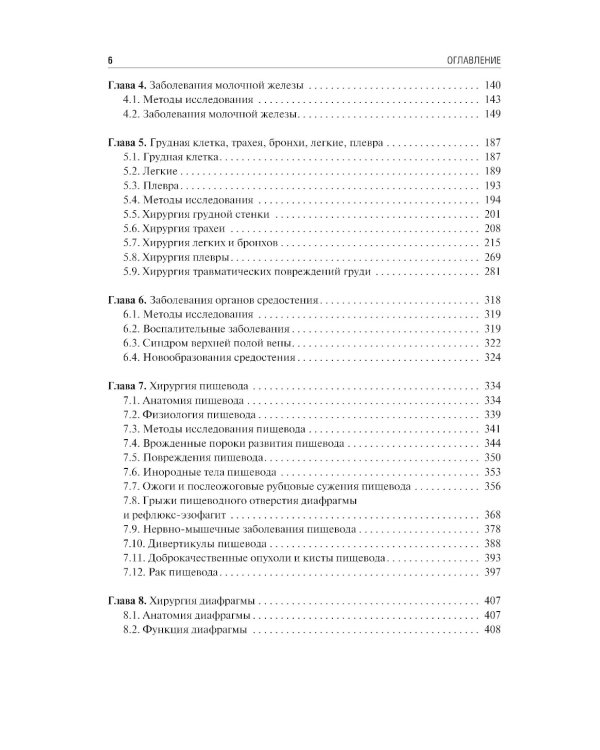

Содержание учебника соответствует программе по факультетской и госпитальной хирургии, а также квалификационной характеристике врача по специальности «Хирургические болезни» и включает главы по хирургической гастроэнтерологии, пульмонологии, кардиологии, ангиологии, флебологии и эндокринологии. В работе над ним принимали участие ведущие специалисты медицинских вузов, институтов РАН, клинических и научно-исследовательских центров. Издание предназначено для самостоятельной теоретической подготовки студентов старших курсов лечебного и педиатрического факультетов медицинских вузов, а также клинических ординаторов и аспирантов системы последипломного образования.| Издательство | ГЭОТАР-Медиа |